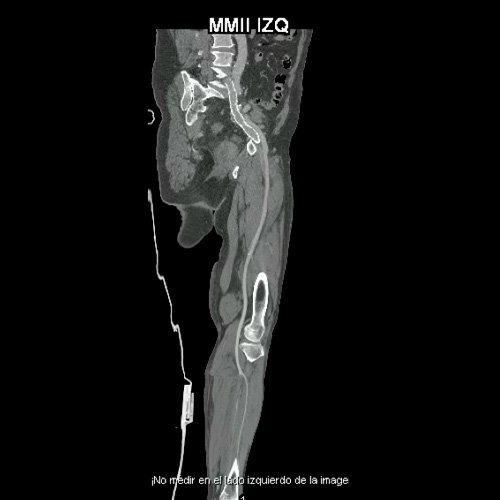

• AngioTAC de miembros inferiores (Día 0): Ateromatosis parietal calcificada parcheada en todo el territorio aorto-ilíaco-femoral bilateral. LADO DERECHO: Arteria ilíaca interna: de calibre y trayecto conservado, permeable. Arterias ilíaca externa y femoral común: de calibre y trayecto conservados, permeables. Arterias circunfleja ilíaca superficial y epigástrica superficial: de calibre y trayecto conservados, permeables. Arteria femoral superficial: de calibre y trayecto conservado, permeable. Arteria femoral profunda: de calibre y trayecto conservado, permeable. Arterias circunflejas femoral medial y lateral: de calibre y trayecto conservados, permeables. Arteria poplítea: de calibre y trayecto conservado, permeable. Arteria tibial anterior: de calibre y trayecto conservado, permeable. Arteria tibial posterior: de calibre y trayecto conservado, permeable. Cambios artrodegenerativos coxo-femorales y tricompartimentales en la rodilla. Signos de entesopatía cuadricipital distal. No se observan alteraciones a nivel de los grupos musculares visualizados. La disposición del tejido graso es normal. LADO IZQUIERDO: En fase angiográfica se observa menor calibre y opacificación de las arterias femoral superficial y profunda, poplítea y de sus ramas musculares en muslo y pierna en comparación con el miembro contralateral, con opacificación arterial preservada. En fase venosa se evidencia mayor la densidad endovascular de las mismas hasta el tercio distal de la pierna, donde se logran identificar a las arterias peronea, tibial anterior y tibial posterior. Se evidencia un defecto de relleno de la vena ilíaca común izquierda, en su nacimiento, en relación a trombosis venosa profunda. No se identifica compromiso de la porción visualizada de la vena cava inferior ni del sistema venoso ilíaco contralateral. Se visualiza aumento del tamaño de todos los grupos musculares del muslo izquierdo con respecto al contralateral y retardo de la concentración de contraste, asociado a edema de los tejidos blandos superficiales. Reticulación de la grasa de la región inguinal. Cambios artrodegenerativos coxo-femorales y tricompartimentales en la rodilla. Signos de entesopatía cuadricipital distal. No se observan alteraciones a nivel del fémur ni de las porciones visualizadas de la tibia y el peroné.

• AngioTAC de miembros inferiores (Día 2): Ateromatosis parietal calcificada parcheada en todo el territorio aorto-ilíaco-femoral bilateral. LADO DERECHO: Arteria ilíaca interna: de calibre y trayecto conservado, permeable. Arterias ilíaca externa y femoral común: de calibre y trayecto conservados, permeables. Arterias circunfleja ilíaca superficial y epigástrica superficial: de calibre y trayecto conservados, permeables. Arteria femoral superficial: de calibre y trayecto conservado, permeable. Arteria femoral profunda: de calibre y trayecto conservado, permeable. Arterias circunflejas femoral medial y lateral: de calibre y trayecto conservados, permeables. Arteria poplítea: de calibre y trayecto conservado, permeable. Arteria tibial anterior: de calibre y trayecto conservado, permeable. Arteria tibial posterior: de calibre y trayecto conservado, permeable. Vena ilíaca primitiva: 13 mm, vena ilíaca externa 11 mm, vena ilíaca interna 7 mm. LADO IZQUIERDO: En esta ocasión, en fase angiográfica se observa de calibre y opacificación conservada de las arterias femoral superficial y profunda, poplítea y de sus ramas musculares en muslo y pierna. En fase venosa se evidencia un defecto de relleno endoluminal de la vena primitiva izquierda que impresiona extenderse actualmente a la vena iliaca externa, a la vena femoral superficial y poplítea, hasta nivel del hueco homonimo, las cuales se visualizan aumentadas de calibre con respecto a sus contralaterales, en relación a trombosis venosa profunda. Se sugiere cotejar con ecodoppler de miembros inferiores. No se identifica compromiso de la porción visualizada de la vena cava inferior ni del sistema venoso ilíaco contralateral. Se visualiza dispositivo vascular en VCI (filtro VCI), infrayacente a las venas renales. Presenta aumento del diámetro del muslo izquierdo con respecto a su contralateral, asociado a edema de los tejidos blandos superficiales. Reticulación de la grasa de la región inguinal a predominio izquierdo con algunas burbujas aéreas. Se observa inmediatamente infrayacente a los antes mencionado, un área hiperdensa que realza en fase venosa, con centro hipodenso, que mide 2.2 cm x 1.4 cm, ya visualizado en tomografía previa. Cambios artrodegenerativos coxo-femorales y tricompartimentales en la rodilla. Signos de entesopatía cuadricipital distal. No se observan alteraciones a nivel del fémur ni de las porciones visualizadas de la tibia y el peroné. Arteria ilíaca interna: de calibre y trayecto conservado, permeable. Arterias ilíaca externa y femoral común: de calibre y trayecto conservados, permeables. Arterias circunfleja ilíaca superficial y epigástrica superficial: de calibre y trayecto conservados, permeables. Arteria femoral superficial: de calibre y trayecto conservado, permeable. Arteria femoral profunda: de calibre y trayecto conservado, permeable. Arterias circunflejas femoral medial y lateral: de calibre y trayecto conservados, permeables. Arteria poplítea, tibial anterior y tibial posterior: de calibre disminuido con respecto a su contralateral, permeables. Vena ilíaca primitiva: 14 mm, vena ilíaca externa 17 mm, vena ilíaca interna 9 mm. Calcificaciones en conducto inguinal bilateral. Hidrocele bilateral.

Angio TAC de miembros inferiores (Día 0)

Angio TAC de miembros inferiores (Día 2)